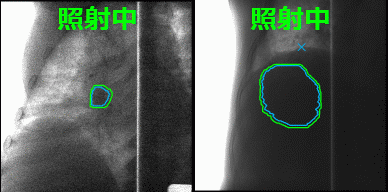

本技術の適用例

重粒子線呼吸同期照射(イメージ図)

肺がん 肝臓がん